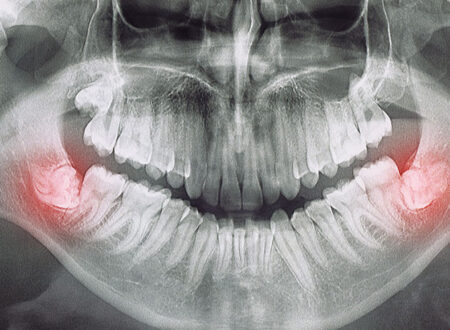

20 Yaş/Gömülü Diş Çekimi

20 Yaş / Gömülü Diş Çekimi Çene gelişimlerinin yeterli olmadığı veya ağız içerisindeki dişlerin boyutunun çene hacmine göre nispeten büyük